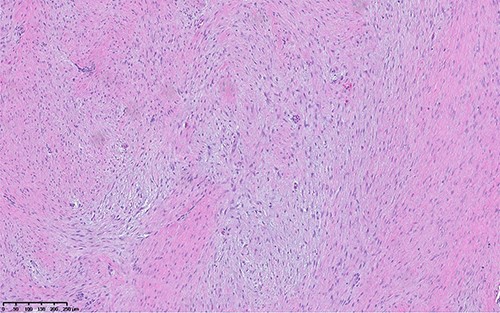

Hematoxylin and eosin image shows hypocellular lesion with long sweeping fascicles of bland spindle cells in background of collagenous and myxoid stroma.

The histologic examination of the resected specimen revealed benign fibroblastic spindle cell tumors focally infiltrating into muscular tissue (Fig. 5). Immunohistochemistry revealed positivity for B-catenin and focal positivity for smooth muscle actin (Fig. 6). Ki-67 proliferation index was low (2%). The spindle cells were negative for desmin, CD34 and keratin. This was consistent with desmoid fibromatosis. The pathological assessment was critical in obtaining a definitive diagnosis.